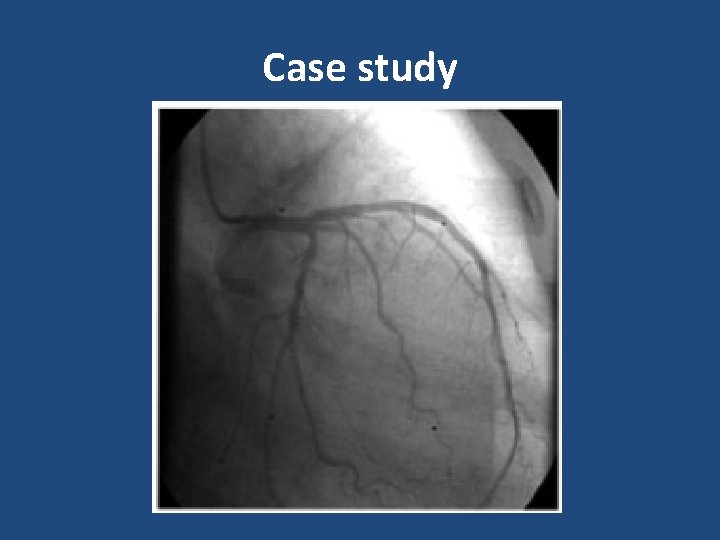

Case study